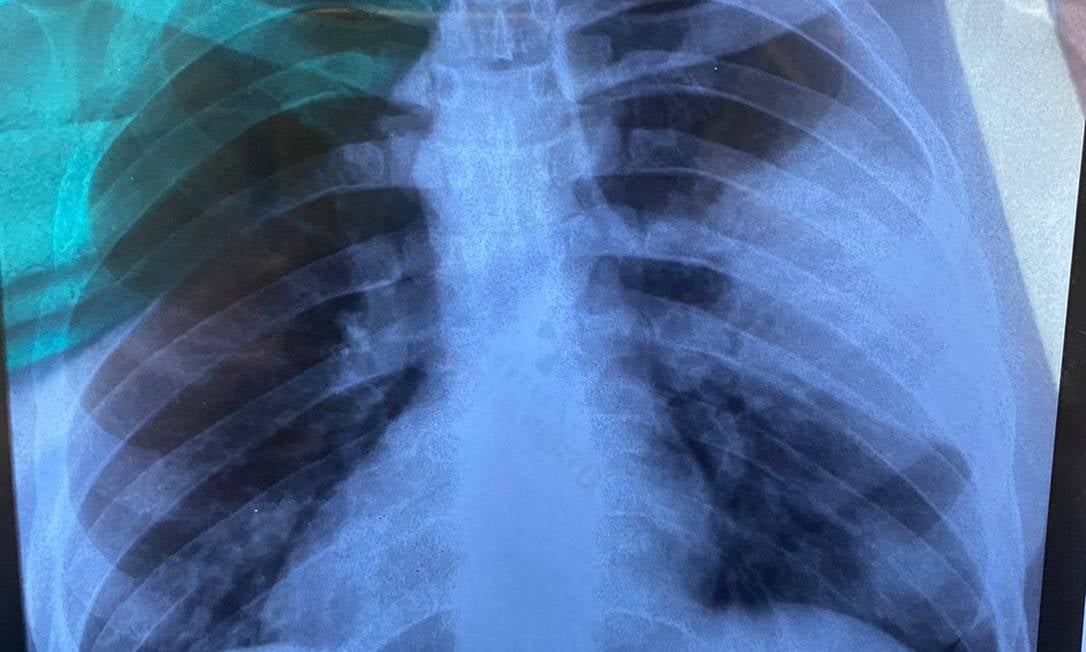

Uma viagem de férias virou um verdadeiro pesadelo para o bancário Allan Douglas, de 30 anos. Natural de Manaus, o jovem estava a passeio no carnaval do Rio de Janeiro quando acordou com fortes dores e tosse seca. Após uma consulta rápida em uma Unidade de Pronto-Atendimento (UPA), foi liberado e retornou para a casa, no Norte do país. Na Quarta-Feira de Cinzas (2), Allan deu entrada em um hospital privado da região e, por uma tomografia, ficou constatado que o pulmão tinha sido perfurado. O jovem não precisou ser entubado, mas ficou três dias na Unidade de Tratamento Intensivo (UTI).

– No dia que voltei do Rio, fui ao trabalho, falei muito e senti falta de ar. Fui ao hospital e me colocaram imediatamente na UTI. O médico foi claro que, se eu não tivesse plano de saúde, poderia ter morrido com a infecção de bactérias – disse Allan, em entrevista ao GLOBO, explicando que o médico deestacou que o tempo de socorro, nestas situações, é determinante para a sobrevivência do paciente.